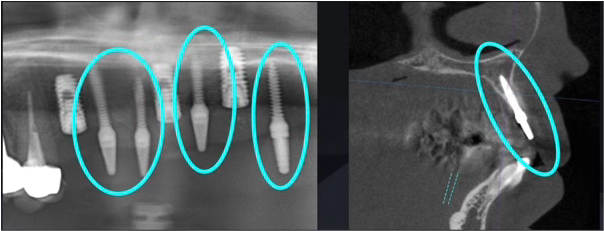

解決策『暫間インプラント』

そこで活躍したのが、『暫間インプラント(テンポラリーインプラント)』です。

これは、細いミニスクリュー状の仮のインプラントで、骨造成中や本インプラントの生着を待つ間に、仮歯を支えるためだけに使用する特殊な装置です。

当院では、この暫間インプラントを積極的に活用し、入れ歯を使わずに美しく・快適に治療を進めるケースを多く行っています。

入れ歯なしで最後まで

今回の患者様は、上顎はオールオン5になるのですが、2本の残根歯と2本の暫間インプラントの合計4本を組み合わせることで、治療期間中も常に仮歯で噛むことができ、一度も入れ歯を使うことなく治療を完了することができました。これは、患者様の強い意志と綿密な治療計画、そして高度な技術のすべてが揃って初めて実現できるケースです。